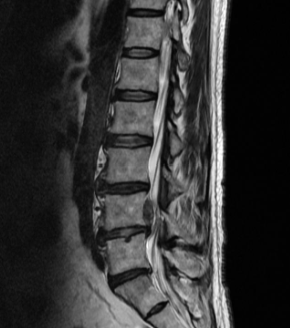

허리디스크를 정확하게 진단하기 위해서는 엑스레이로는 힘들며, MRI를 통해 검사해야 정확하게 볼 수 있습니다.

MRI가 몸에 좋지 않지만 허리 통증으로 엑스레이만 진행 할 경우 오진이 많아 지속적인 통증이 계속 된다면 허리디스크를 의심하고 MRI 검사를 한번 받아보시길 권유드립니다.